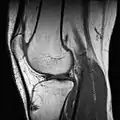

Ressonância magnética (RM) de um joelho.

RM de um joelho.